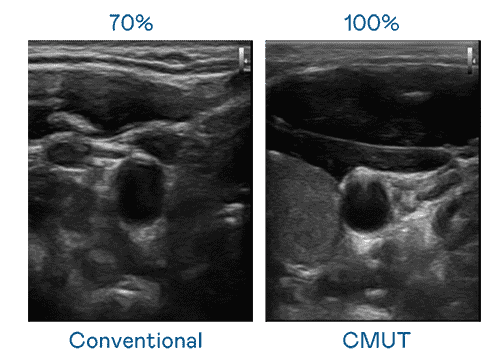

CMUT 技术是一种用电容式微机电元件来产生超音波讯号的技术。。。。与传统 PZT 压电式技术相比,,,,CMUT 频宽增加 30%,,更宽频的超音波讯号让影像解析度大幅提升,,,是实现高影像品质医疗超音波扫描、、、促进精准医疗发展的关键技术。。

大频宽带来超清晰影像

超音波影像的解析度高低,,,首先取决于探头能发出的讯号频宽。。传奇国际 CMUT 可提供高清晰的超音波讯号,,,,提供高频宽、、高灵敏度、、影像纹理细节更高的超音波影像,,协助医护人员缩短影像判读时间及利用精准的医疗影像进行诊断。。